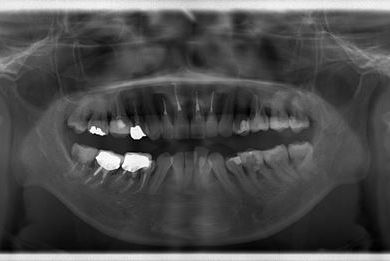

セラミックの症例写真 SHINBI

セラミック治療

| 治療方針 | 上顎前歯をセラミック治療にて審美的回復を行う。 | ||||||||||||||||||||||||||||||||

| 治療内容 | オールセラミッククラウン4本(セラミック用土台4本) | ||||||||||||||||||||||||||||||||

| 総治療費 | 573,300円 | ||||||||||||||||||||||||||||||||

| 治療期間 | 3ヶ月 |